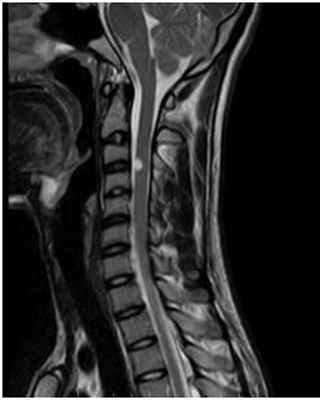

МРТ краниовертебрального сочленения в сагиттальной плоскости (А) и художественное исполнение (Б).

Показаны покровная мембрана (стрелка) и поперечная связка атланта (толстая стрелка).

БА — базион; ОП — опистион; ПМем — передняя атланто-затылочная мембрана; ЗМем — задняя атланто-затылочная мембрана;

З—Зуб; Ост2 — остистый отросток С2;ПД — передняя дуга атланта (тонкая стрелка); ЗД — задняя дуга атланта. Крестообразная, поперечная, крыловидные и добавочные связки.

МРТ снимок шейного отдела позвоночника с захватом краниовертебрального перехода

МРТ головного мозга — белыми линиями отмечен краниовертебральный переход